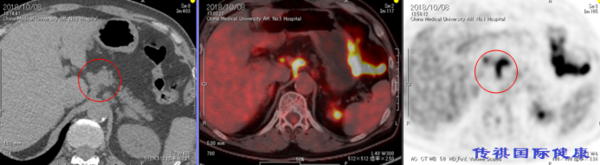

B: 5 . 可见上肠间间膜动脉处右侧大动脉淋巴节的FDG集聚。淋巴节有转移巢的可能性。

C: 6和7,.在气管分歧周围的淋巴节上可见FDG集聚。淋巴节有转移巢的可能性。

例如,在对A病灶靶区的最新一代M6型机型可跟踪呼吸机能的高精准放射线(全日本仅3台)治疗之后,立刻接受免疫(PD-1)治疗第1次,对B病灶靶区的高精准放射线治疗之后也立刻进行免疫(PD-1)治疗第2次。对C病灶靶区的高精准放射线治疗之后立刻接受免疫(PD-1)治疗第3次(每2次免疫PD-1之间需要间隔2周),再组合免疫细胞疗法的话对预后会更理想。